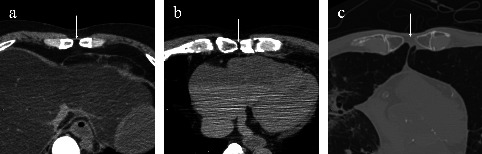

Results: Sternal foramina were present in 3.7% of adults. They were more frequent in males (4.3%) than in females (2.5%), although the difference was insignificant. Most foramina were located at the level of the fifth costal notch and overlaid the pericardium or lung in 72% of evaluable cases. The median diameter was 4.5 mm. In pediatric cases, 11 (12%) exhibited lower-sternebral ossification-center patterns that could form sternal foramina, supporting a developmental origin. An estimated 31% of these patterns may persist into adulthood with unfused segments.

Conclusion: Sternal foramina occurred in 3.7% of adults and were often situated over vital structures, posing procedural risks. Among pediatrics, ossification patterns that may impede fusion-defined as horizontal two-center or ≥ 3 center configurations-were present in 12%, and approximately 31% of these patterns appear to persist into adulthood as sternal foramina. These findings support a developmental basis for sternal foramina and emphasize the importance of recognizing them during imaging and procedural planning.